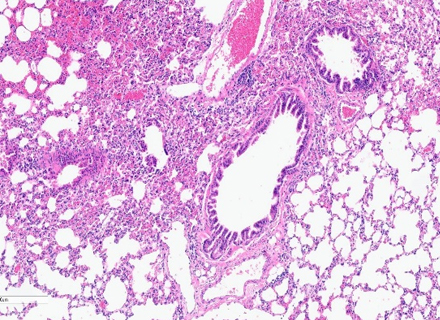

H&E staining :

Clear visualization of tissue structure

Cell distribution

Morphological changes within tissue samples